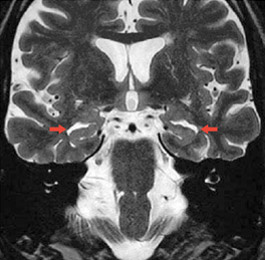

mri_alzheimer_typisch

Abb. 1a

MR-Bilder zweier Patienten mit Demenzerkrankung: typischer Befund einer Alzheimer-Erkrankung mit deutlich erweiterten Hirnkammern (rote Pfeile)